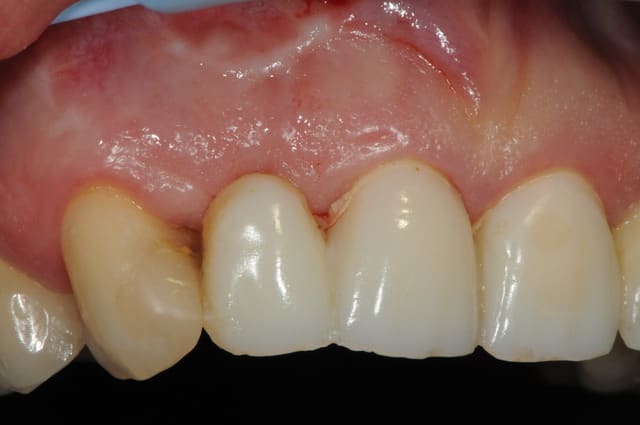

deux mois après (photo 2-3-4), l'état de la gencive me paraît plutôt sympa et je propose donc d'en rester là. toutefois la patiente ne veut pas, elle à peur de perdre le bridge (même le définitif) , bref, elle veut un implant !

voici - voilà:

photo

1: j+ 2 ou 3 jours

2: j+8 mois

3-4-5: j+ 2 ans

sur la photo 3 on voit à la gencive que l'aspect est moins granité au niveau du col.

c'était ça l'indice pour trouver Charlie.